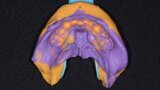

Fig. 7: Maxillary impression (Kettenbach).